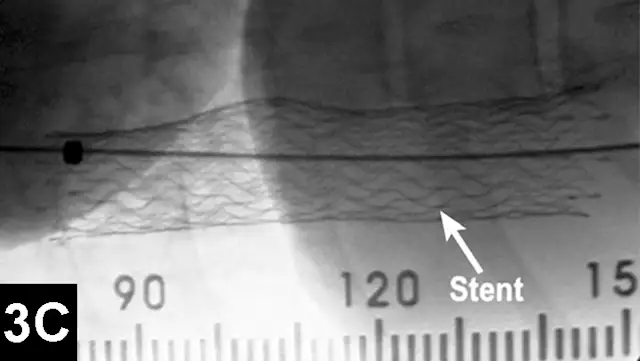

Tracheal collapse is characterized by clinical signs such as cough, raspy breathing, and dyspnea. Signs can often be treated palliatively with cough suppressants, bronchodilators, sedatives, tranquilizers, or NSAIDs, yet adequate control of disease is not always possible. Candidates for surgery include patients in which initial conservative medical management has failed. However, excessive morbidity and mortality rates have been reported for the extraluminal ring prosthesis open surgical procedure.3

Clinical improvement can be achieved in 75% to 90% of animals treated with self-expanding metallic stents (Figure 1), an IR procedure.4 Immediate adverse events were mostly minor; however, a perioperative mortality rate of about 10% was reported. Longer-term adverse events included shortening of the stent, fracturing of the stent, progressive tracheal collapse, and excessive granulation tissue.

Figure 1A: Serial lateral fluoroscopic images of a dog with tracheal collapse.

A positive pressure ventilation demonstrates maximal dilation of the trachea. A marker catheter in the esophagus is used to account for radiographic magnification.